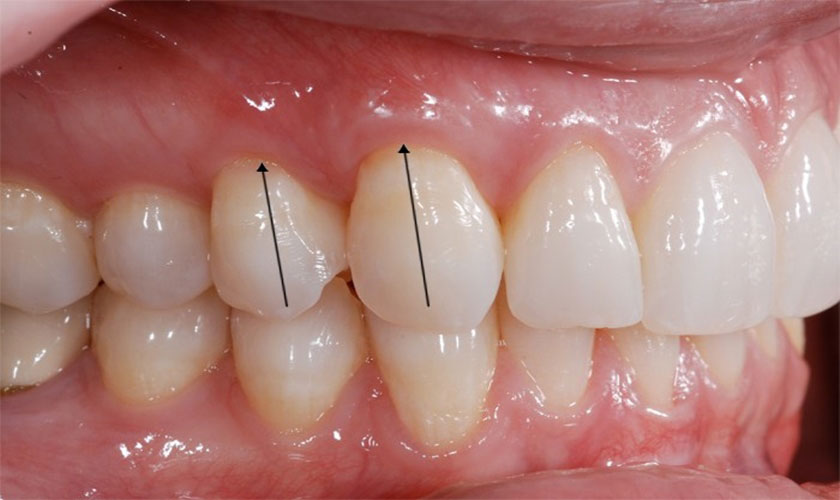

Nướu răng chắc khỏe là nướu răng có màu hồng nhạt hoặc màu hồng có pha lẫn với màu trắng ở phía dưới chân răng, các “gai nướu” có dạng đỉnh nhọn.

Khi nướu bị vi khuẩn tấn công, nướu sẽ chuyển dần từ màu hồng nhạt sang màu đỏ và đỏ sậm tùy theo tình trạng viêm nhiễm của nướu

Nhận biết tình trạng nướu bị sưng đỏ